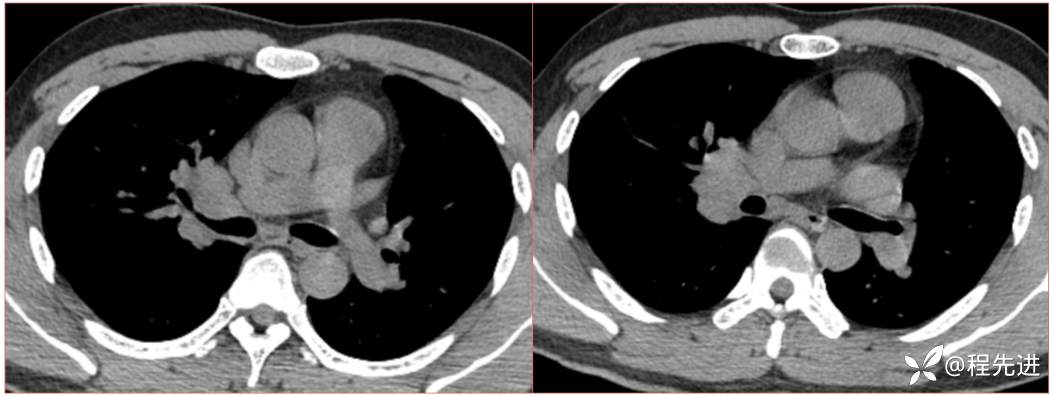

2023国庆特别精彩病例(一)|阵发性刺激性咳嗽,咳少量白色粘液痰1周|结果已公布

患者年龄:34岁

简要病史:患者一周前无明显诱因出现阵发性刺激性咳嗽,咳少量白色粘液痰,咳嗽无明显昼夜节律性,无发热、畏冷、寒战,无头痛、胸闷、胸痛,自行服药后 (具体不详) 症状无缓解,3天前外院胸片检查示右上病变

辅助检查:肺肿瘤标志物:神经元特异性烯醇化酶(NSE):35.72ng/ml(参考值0-16.3);非小细胞肺癌相关抗原211、胚抗原糖类抗原125、铁蛋白、鳞状细胞癌抗原未见异常